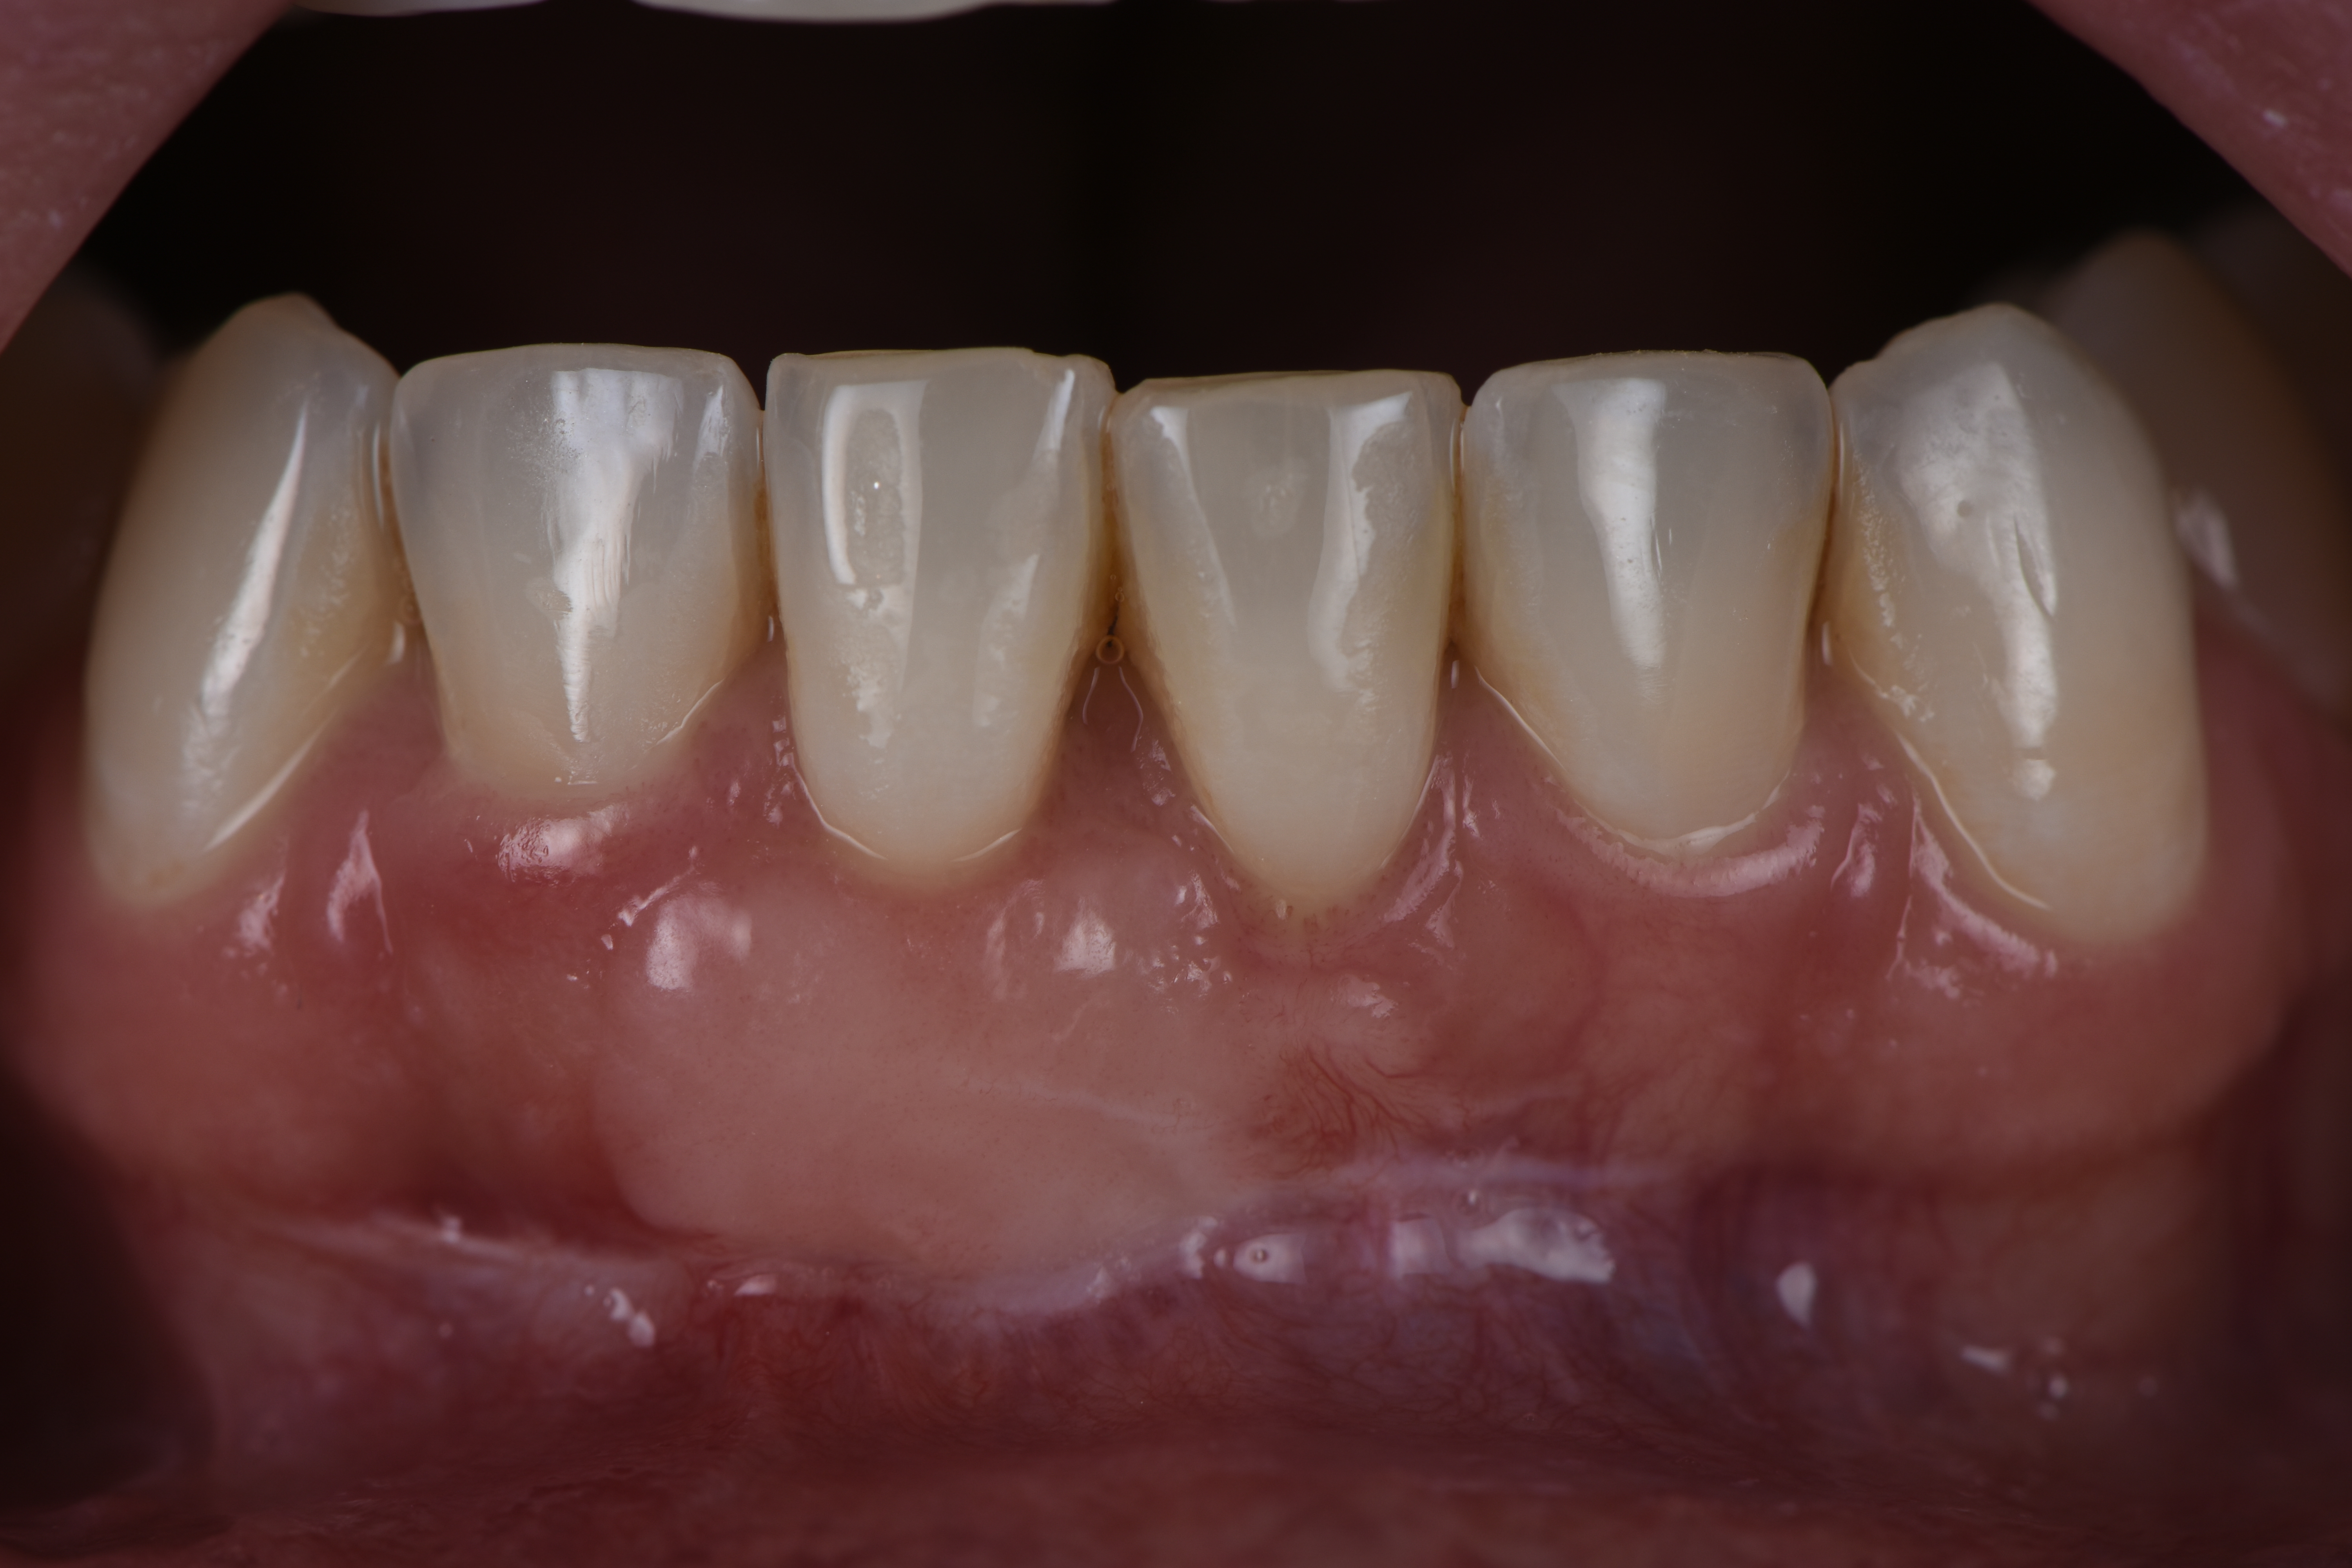

Una vez que hemos perdido encía y se ha quedado la raíz dental expuesta, podemos realizar cirugía mucogingival para volver a recuperar la estética y salud de nuestro periodonto.

Casos clínicos realizados por el Dr. Alfonso García

Déspues

Caso 1